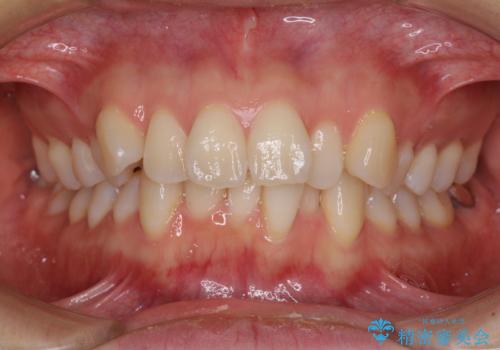

前歯のデコボコを抜歯矯正で改善 メタル装置で費用を抑える

- 前歯のデコボコと口元の突出感を気にして来院された患者様です。

もう少し口元の突出感を改善したかったのですが、舌の突出癖が影響し下顎前歯が唇側に押させる仕上がりとなりました。